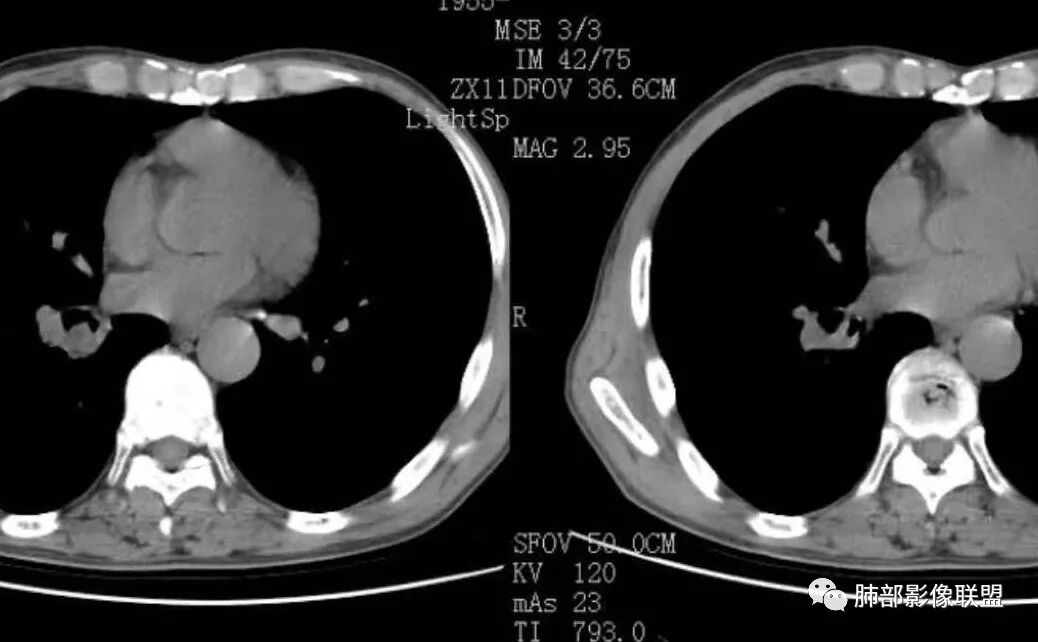

右肺下叶支气管腔内肿块,沿着支气管生长,支气管壁破坏,中度强化,纵膈及肺门淋巴结肿大,老年男性,首先考虑小细胞肺癌,其次腺样囊腺癌。类癌女性多见,明显强化,淋巴结肿大少见。鳞癌常有远端阻塞炎症及肺不张,淋巴结肿大少见。

右肺下叶支气管开口新生物,轴位管腔及纵向基底干大部分受累狭窄,支气管管壁破坏并突破形成腔外肿块,血管累及变细,肉眼观轻度强化,右肺门、纵膈淋巴结肿大,恶性没问题,阻塞性炎症不明显,类癌强化明显不支持,老年男性,首先考虑小细胞癌,鉴别不典型鳞癌和腺癌。

右肺下叶支气管内新生物,破坏管壁向腔外膨胀生长,累及各基底段开口,无明显坏死,有局部强化,远端无明显阻塞,右肺门及纵隔淋巴结肿大,考虑恶性可能大,对临床来说,非常简单,纤支镜直接取病理活检就完事了,但病理分型对影像来说就比较纠结了,小细胞?类癌?粘表?腺样囊腺癌?低分化腺癌?鳞癌?只有暂时把小细胞考虑到前面,其他待排,等纤支镜活检确定。

右肺下叶开口支气管内新生物,破坏管壁向腔外膨胀生长,累及各基底段开口,无明显坏死,有局部强化,远端无明显阻塞,右肺门及纵隔淋巴结肿大,考虑恶性肿瘤。大气道肿瘤不支持腺癌。小细胞癌大多为周围病灶引起肺门、纵隔淋巴结转移,肺门淋巴结明显肿大后侵犯支气管粘膜到达支气管内(从外到内),本例病灶从管腔内向腔外长,不支持小细胞癌。病灶为轻→中度强化,类癌显著强化为主→不支持,鳞癌、腺样囊性癌一般中度强化,鳞癌大多有阻塞性病变,本例无明显阻塞不支持鳞癌。粘液表皮样癌一般为轻度不均匀强化。感觉病灶为轻中度不均匀强化。综上首先考虑粘表,其次腺样囊性癌。待支气管镜活检明确。